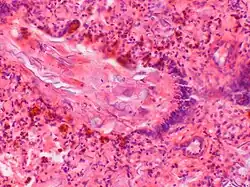

Zespół aspiracji smółki (ang. meconium aspiration syndrome, MAS) – powikłanie niedotlenienia wewnątrzmacicznego, polegające na aspiracji wód płodowych przez płód wraz z oddaną przedwcześnie smółką. Zarówno oddanie smółki jak i głębokie ruchy oddechowe płodu spowodowane są niedotlenieniem i odruchem z nerwu błędnego.